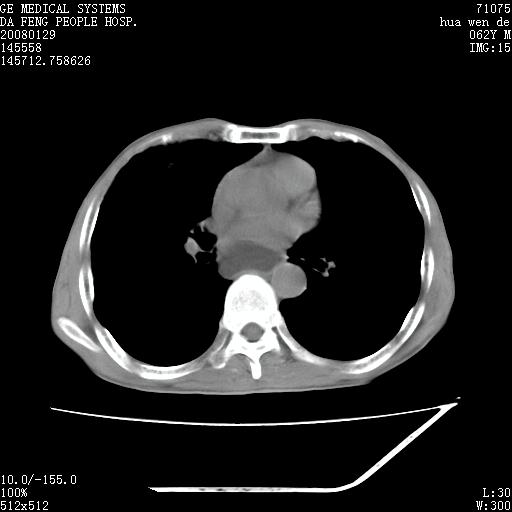

男性,67岁。作肺部检查时发现

1.整个食管扩张,未见明显占位性病变,贲门区亦未见明显占位病变,考虑:贲门失驰缓症;

2.右上肺病变边缘可见毛刺,囊壁厚度不均匀,周围境界较清楚,未见炎性渗出性影,右上肺外带可见片状影,边缘不清,考虑:肺癌伴空洞形成、右上肺炎。

食管全程扩张,壁均匀不厚,喷门失弛缓症

右上肺空洞可见液平,临近肺野磨玻璃密度,考虑1.结核2.脓肿

贲门失驰缓症.肺部感染伴脓肿形成。支持!是否吸入性要结合临床诊断,我们影像是看不出来的。但胸腔胃能排除(1.没有手术史支持,2.双侧胸廓对称,胸壁、肋骨及胸膜规整,3,食管壁明显扩张内壁光滑,胸腔胃黏膜皱襞多较厚)。